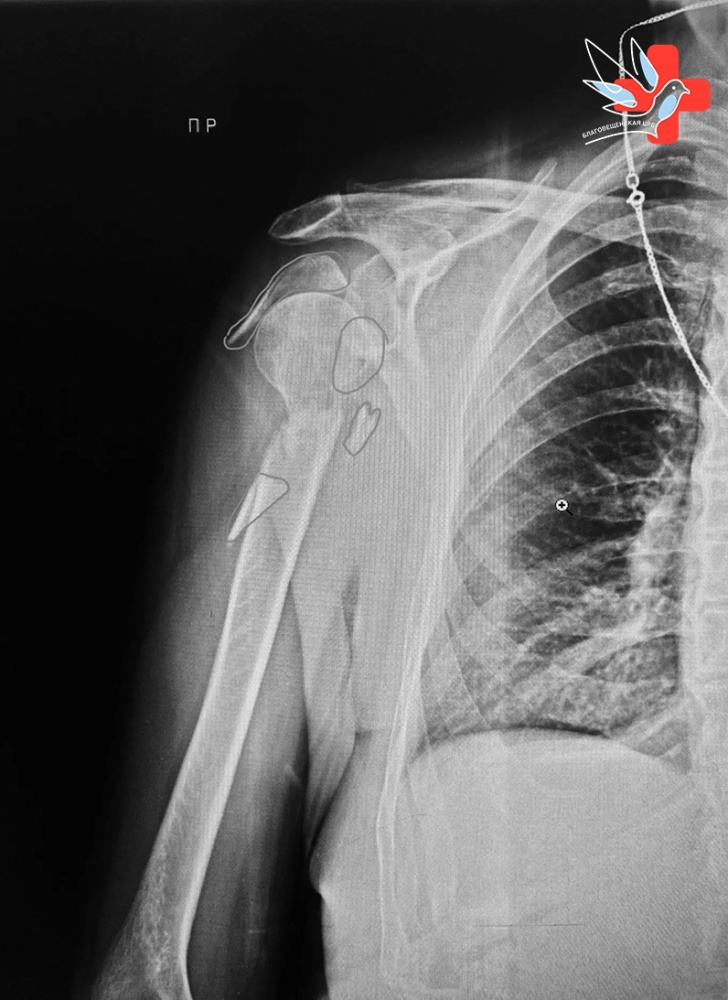

30 января в травматологическое отделение Благовещенской больницы экстренно поступила 78-летняя пациентка после падения дома. Диагностирован перелом плечевой кости, требующий оперативного вмешательства.

Врач-травматолог Сараж Багаутдинович Измайлов успешно провёл сложную операцию — остеосинтез с применением титановой пластины. Благодаря профессионализму доктора и слаженной работе медицинского персонала, пациентка уже выписана домой с положительной динамикой.